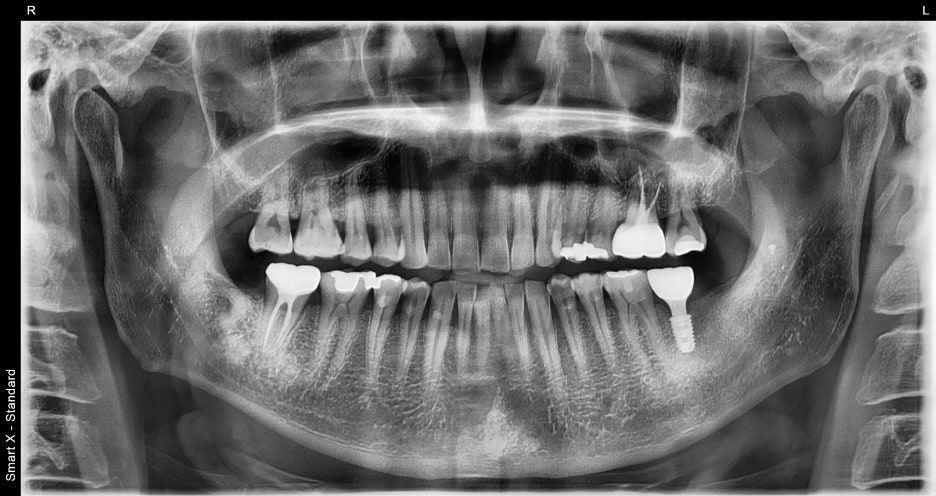

치료결과

양쪽으로 고르게 씹을 수 있어서

턱이 훨씬 편해졌어요

환자분은 수술 후 “양쪽으로 고르게 씹을 수 있어서

턱이 훨씬 편해졌다”며 만족감을 보이셨습니다.

심미적으로도 자연스러운 크라운이 장착되어

주변에서 전혀 티가 나지 않았습니다.